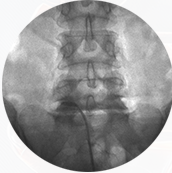

좁아진 신경 통로에 풍선 카테터를 넣어 공간을 넓히고 약물을 주입해,

다리 통증과 저림을 줄이는 최소침습 척추 시술입니다.

가느다란 카테터를 경막외 공간에 넣어 목(경추)·허리(요추) 신경 주변 유착과 염증을 풀어주고,

통증을 완화하는 최소침습 척추 시술입니다.